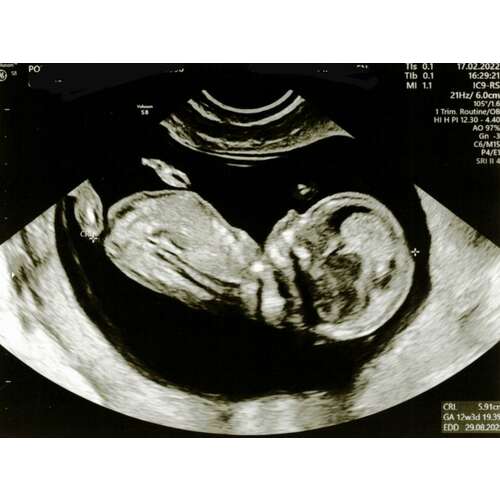

Hier ben ik 11+4, ik weet dat het iets te vroeg is, maar is er al iets te zien?

Hoi hoi! Ben super benieuwd wat jullie denken. Echo 13+3 💖💙?

Hoi nubster🙂 ik heb nog 2 andere echo foto’s. Misschien zijn deze iets duidelijker? Baby’tje ligt wel ietsjes naar z’n linkerzijde